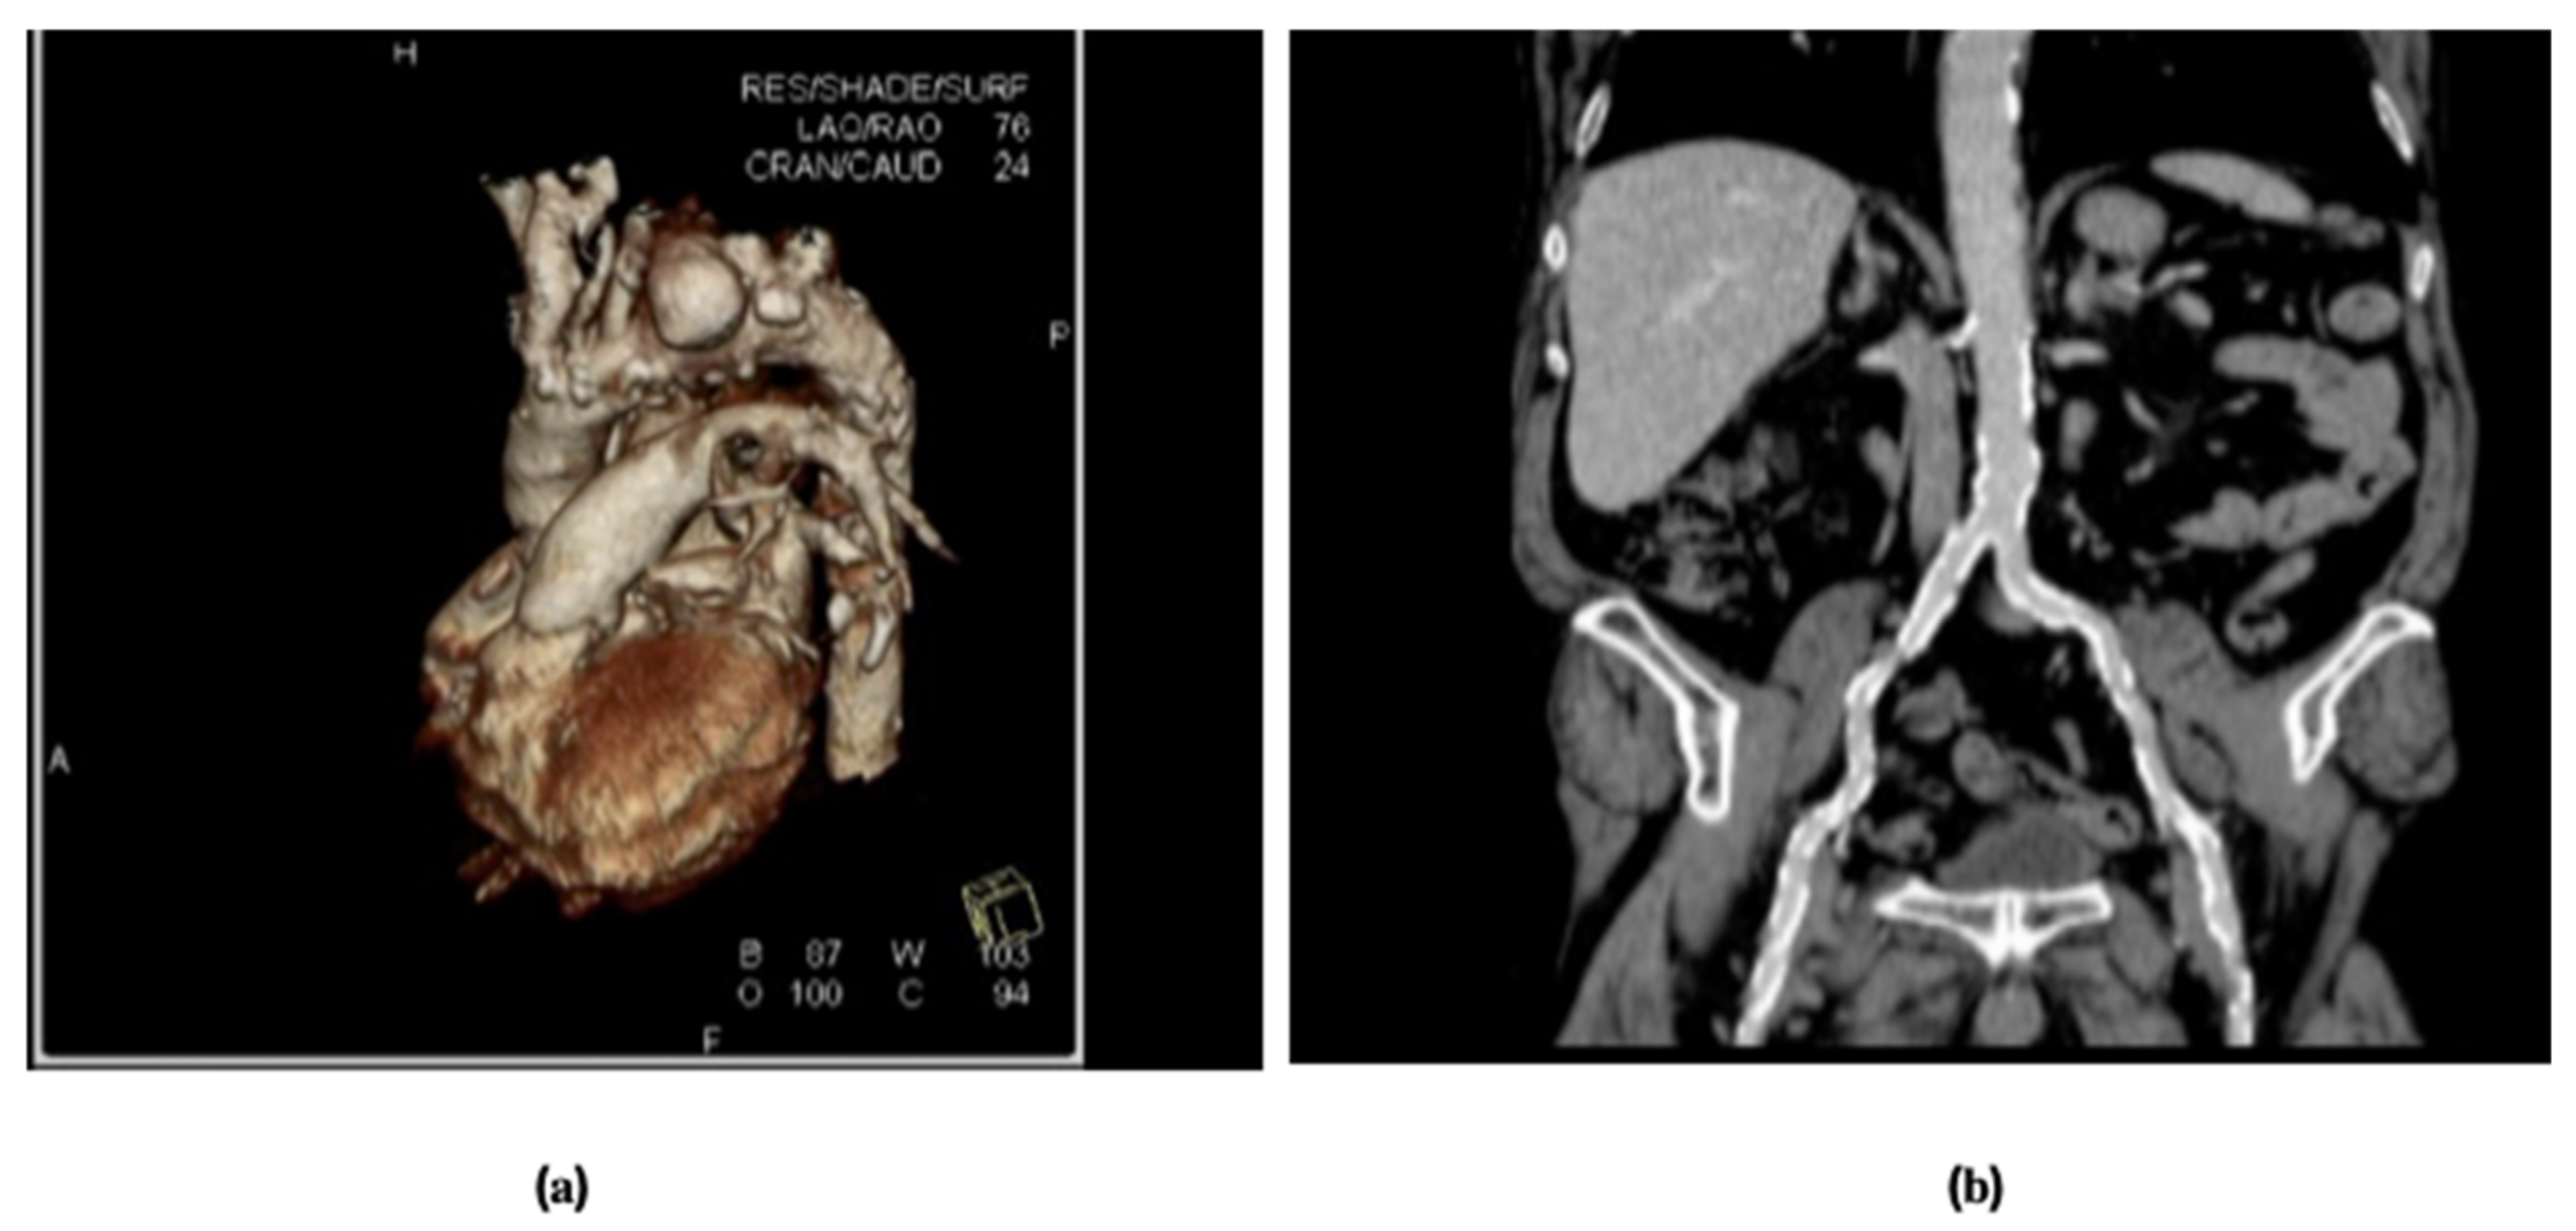

- Murakami, T.; Nishimura, M.; Hosono, M.; Nakamura, Y.; Sohgawa, E.; Skai, Y.; Shibata, T. Transapical endovascular repair of thoracic aortic pathology. Ann. Vasc. Surg. 2017, 43, 56–64. [Google Scholar] [CrossRef] [PubMed]

- Borrello, B.; Nicolini, F.; Agostinelli, A.; Gherli, T. Cardiac transapical approach: A new solution for the treatment of complex thoracic aortic disease. J. Thrac. Cardiovasc. Surg. 2012, 144, E123–E125. [Google Scholar] [CrossRef]

- Agostinelli, A.; Carino, D.; Borrello, B.; Romano, G.; Palumbo, A.A.; Marcato, C.; Gherli, T.; Nicolini, F. Thoracic endovascular aortic repair through cardiac apex in the setting of thoracic artic rupture. Ann. Thorac. Surg. 2018, 106, e177–e178. [Google Scholar] [CrossRef] [PubMed]

- Agostinelli, A.; Carino, D.; Borrello, B.; Nicolini, F. Transapical access for thoracic endovascular aortic repair to elephant trunk completion. Interact. Cardiovasc. Thorac. Surg. 2018, 27, 301–303. [Google Scholar] [CrossRef]

- Venturini, J.M.; Milner, R.; Shah, A.P. Percutaneous transapical access to facilitate complex thoracic endovascular aortic repair. J. Vasc. Surg. Cases Innov. Tech. 2019, 21, 205–209. [Google Scholar] [CrossRef]